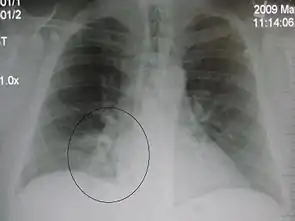

A chest X-ray showing a very prominent wedge-shape bacterial pneumonia in the right lung